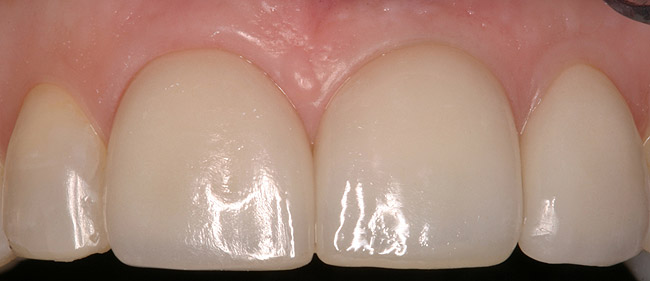

Figure 5d  Completed, porcelain-fused-to-gold implant restorations, custom gold abutments, lingual-set screw-retention, Kerr Extrude¬Æ light-body crown-abutment seal.

Figure 5d

Figure 5e  Completed, porcelain-fused-to-gold implant restorations, custom gold abutments, lingual-set screw-retention, Kerr Extrude¬Æ light-body crown-abutment seal.

Figure 5e

Figure 5f  Completed, porcelain-fused-to-gold implant restorations, custom gold abutments, lingual-set screw-retention, Kerr Extrude¬Æ light-body crown-abutment seal.

Figure 5f

Figure 5g  Completed, porcelain-fused-to-gold implant restorations, custom gold abutments, lingual-set screw-retention, Kerr Extrude¬Æ light-body crown-abutment seal.

Figure 5g